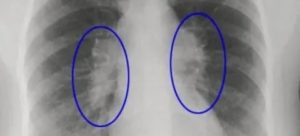

1. Рентген легких.

Позволяет установить наличие воспаления и расположения очага патологического процесса.

Во время осмотра при аускультации легкое не прослушивается, при перкуссии отмечается притупление звука, на обзорной рентгенограмме визуализируется обширное затенение — линия Дамуазо, соответствующая уровню жидкости.

На рентгенограмме грудной клетки при пневмотораксе видна значительная область просветления, органы средостения при этом смещены в противоположную сторону.